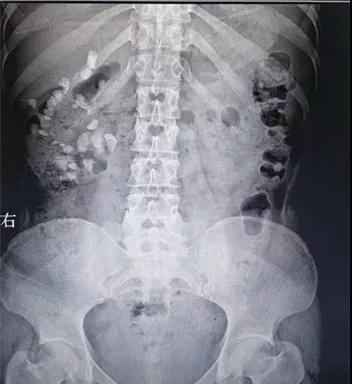

王女士今年23歲,前段時(shí)間總是腰痛難忍,一度出現(xiàn)血尿,來(lái)到徐州市礦山醫(yī)院泌尿外科就診,檢查發(fā)現(xiàn),其右腎臟上中下盞幾乎都有結(jié)石,最大的一顆直徑長(zhǎng)2.3CM,差不多一元硬幣大小,且有腎積水。

“常規(guī)通道經(jīng)皮腎鏡出血風(fēng)險(xiǎn)較大,單獨(dú)做經(jīng)皮腎鏡碎石術(shù),不能完全清除結(jié)石,同時(shí)結(jié)石負(fù)荷大,腎小盞盞口狹窄,也不適合單做輸尿管軟鏡。”泌尿外科李永主任解釋道。

面對(duì)如此棘手的疑難病例,術(shù)前李永主任組織泌尿外科全體醫(yī)師進(jìn)行周密而又嚴(yán)謹(jǐn)?shù)挠懻摗?/span>對(duì)患者病情進(jìn)行詳細(xì)評(píng)估,與患者及家屬充分的溝通后,決定取側(cè)仰臥奔跑位為其實(shí)施微通道輸尿管軟鏡聯(lián)合經(jīng)皮腎鏡右腎結(jié)石碎石取石術(shù)。

手術(shù)分兩組人員進(jìn)行,一組經(jīng)輸尿管留置軟鏡鞘,軟鏡觀察腎臟各盞結(jié)構(gòu),另一組人員經(jīng)皮膚穿刺“打洞”至目標(biāo)腎盞,即腰部經(jīng)皮腎鏡打洞聯(lián)合經(jīng)尿道輸尿管軟鏡碎石。通過(guò)輸尿管軟鏡將位于下盞結(jié)石移位至腎盂及穿刺腎盞,然后利用經(jīng)皮腎鏡通道,鈥激光擊碎結(jié)石并取出。

此舉大大地縮短了手術(shù)時(shí)間、提高了清石效率,同時(shí)降低了腎盂壓力,減少了手術(shù)感染的風(fēng)險(xiǎn)。在麻醉科的大力配合下,手術(shù)僅用了1個(gè)多小時(shí),術(shù)中引流通暢,出血少,完全清除干凈結(jié)石,手術(shù)過(guò)程順利,術(shù)后當(dāng)天患者就能下床走動(dòng),3天后康復(fù)出院。